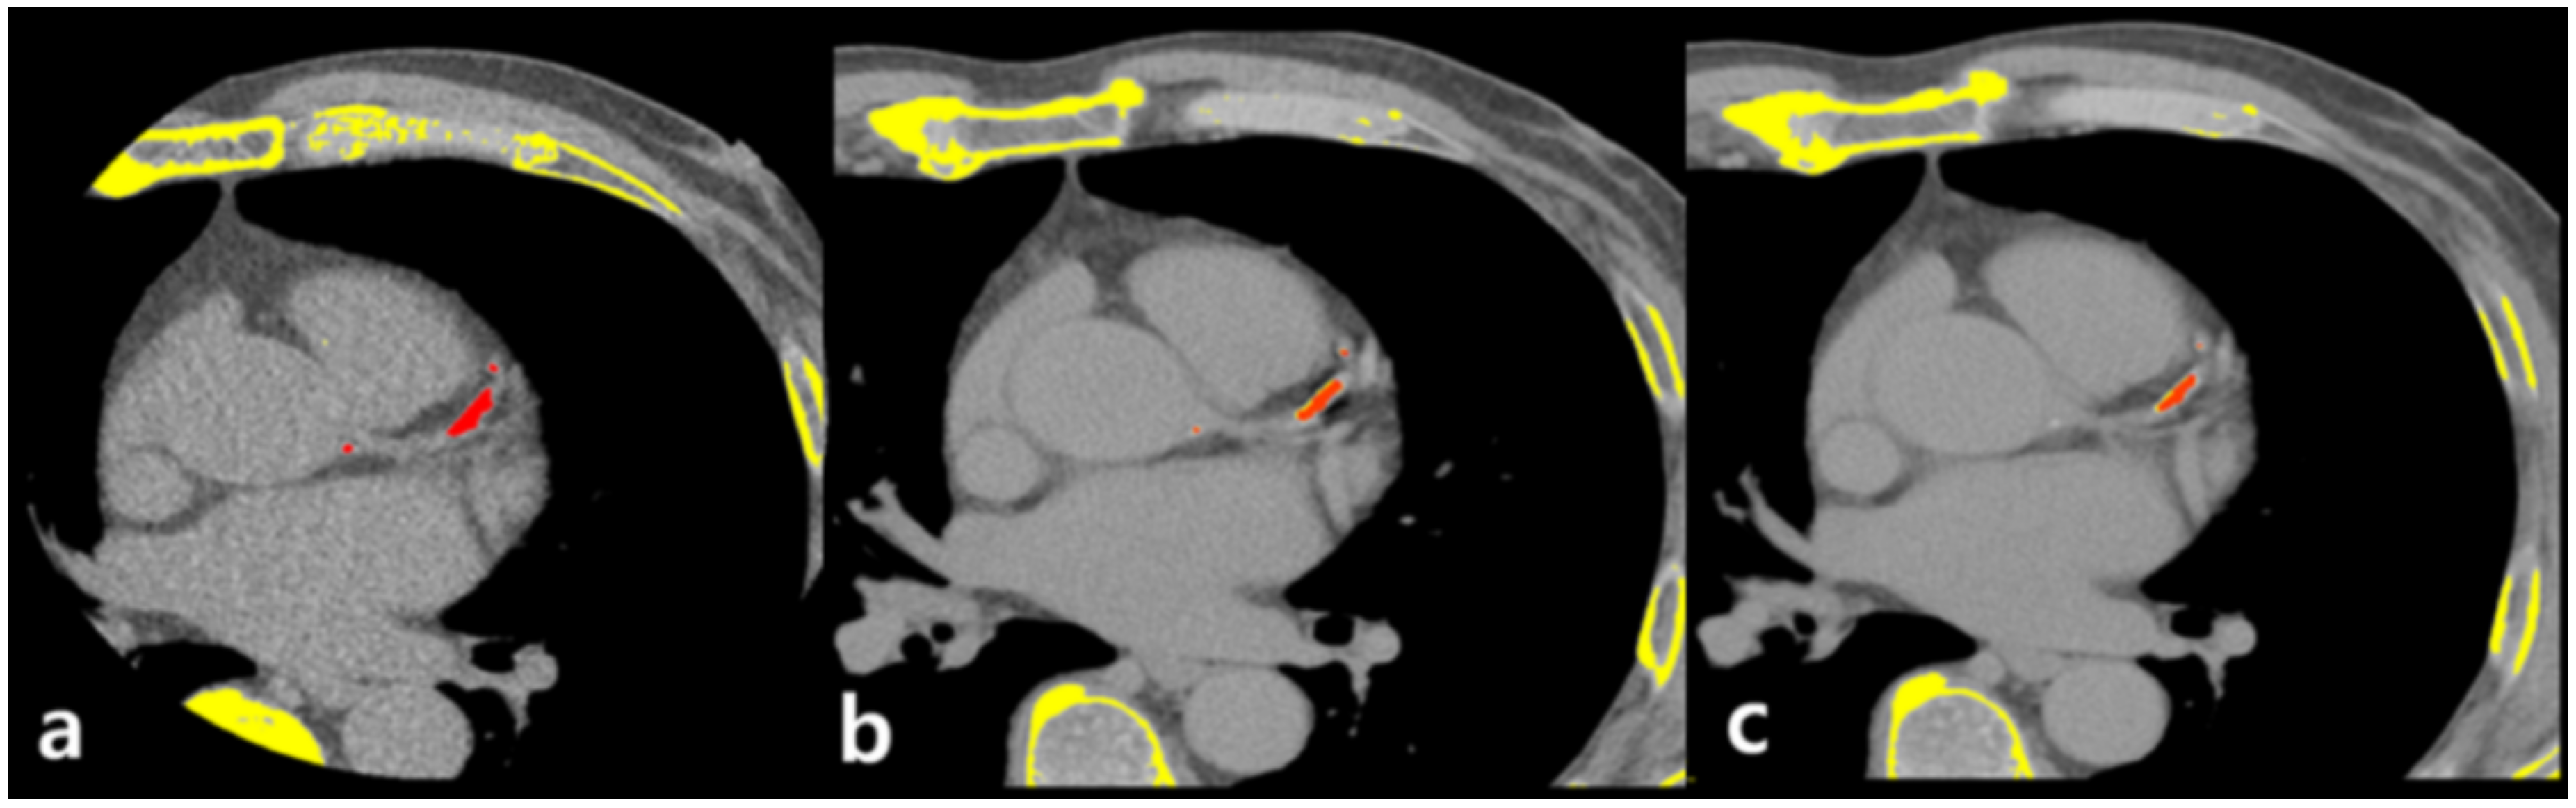

Two radiologists (C.H.P. and T.H.K) with >10 years of experience in chest and cardiac imaging interpretation evaluated all CT images based on consensus. CACSs were acquired with the Agatston method, using a commercially available reconstruction program for three-dimensional reconstruction and measurement (Aquarius iNtuition TM Ver.4.4.12 TeraRecon, Foster City, CA, USA). In this program, regions where the HU value is higher than 130 are displayed in yellow and are selected if they were considered as coronary calcium after reviewing slice by slice on axial images (Figure 3).

This program subsequently calculates the calcium score automatically. The Agatston scoring method, along with the multiplication of calcification areas and weights (1 = 130 to 199 HU, 2 = 200 to 299 HU, 3 = 300 to 399 HU, and 4 = 400 HU or higher), was automatically processed through the program. Images of ECG-gated non-enhanced coronary calcium-scoring CT and VUE images of chest DECT of 1.25 mm and 2.5 mm slice thickness were all analyzed.

Figure 3. Representative case of coronary calcium scoring on calcium-scoring CT and chest dual energy CT. Pixels with HU > 130 are displayed in yellow and red if selected as calcium by operator. Calcium is well visualized on calcium-scoring CT (a), 1.25 mm slice thickness VUE image of chest DECT (b), and 2.5 mm slice thickness VUE image of chest DECT (c).